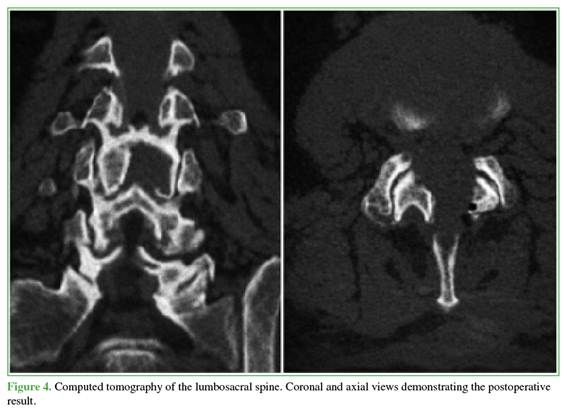

The findings were consistent with a hemorrhagic juxtafacet synovial cyst. Given the acute presentation with progressive motor neurological deficit and severe radicular compression, the patient underwent urgent decompression. The objective was to relieve neural compression, reverse the motor deficit, and allow rapid functional recovery while minimizing invasiveness. A posterior interlaminar uniportal endoscopic decompression was performed using a contralateral (left-sided) approach and the “over-the-top” technique (above the dural sac) to achieve safe and complete cyst resection (Figures 2-5).

The procedure lasted 95 minutes. Blood loss was minimal and not quantifiable, and no intraoperative complications occurred.